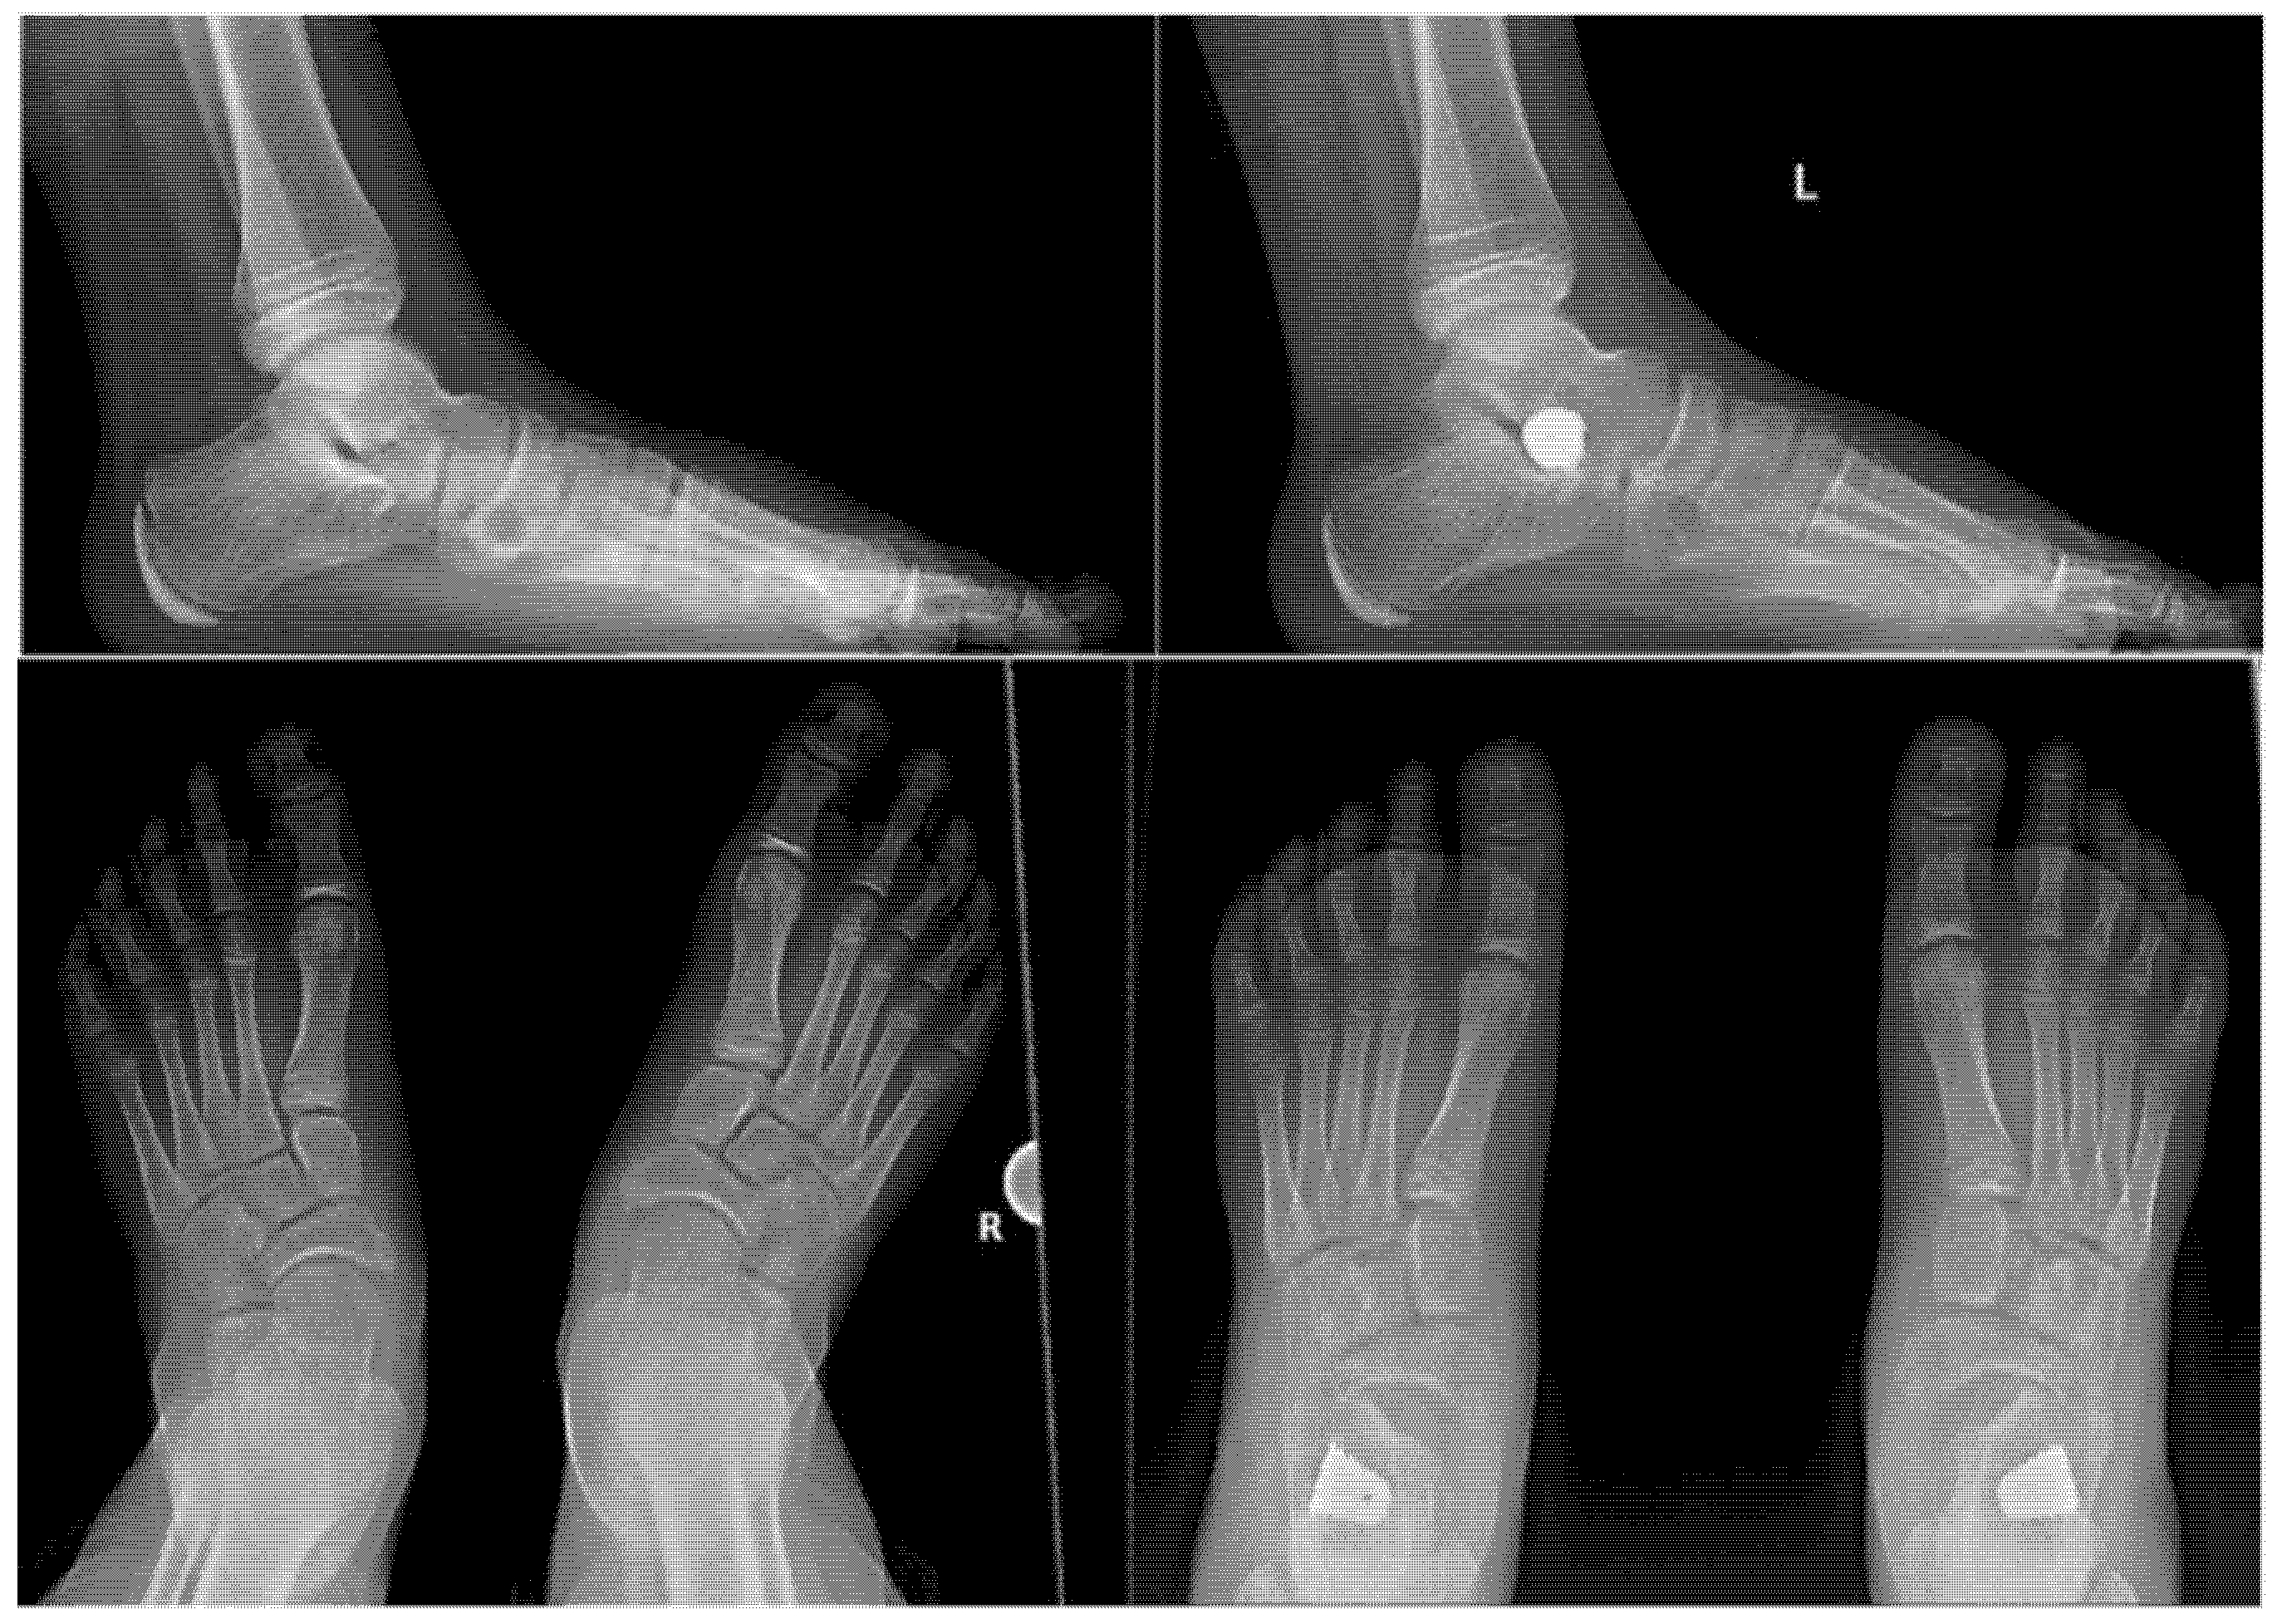

2.4. Surgical Procedure